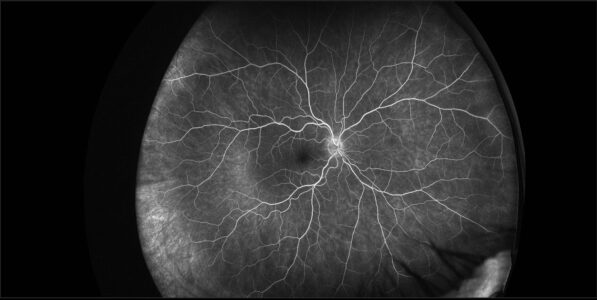

Image d’angiographie à la fluorescéine ultra-grand-champ

montrant une vascularisation rétinienne normale.